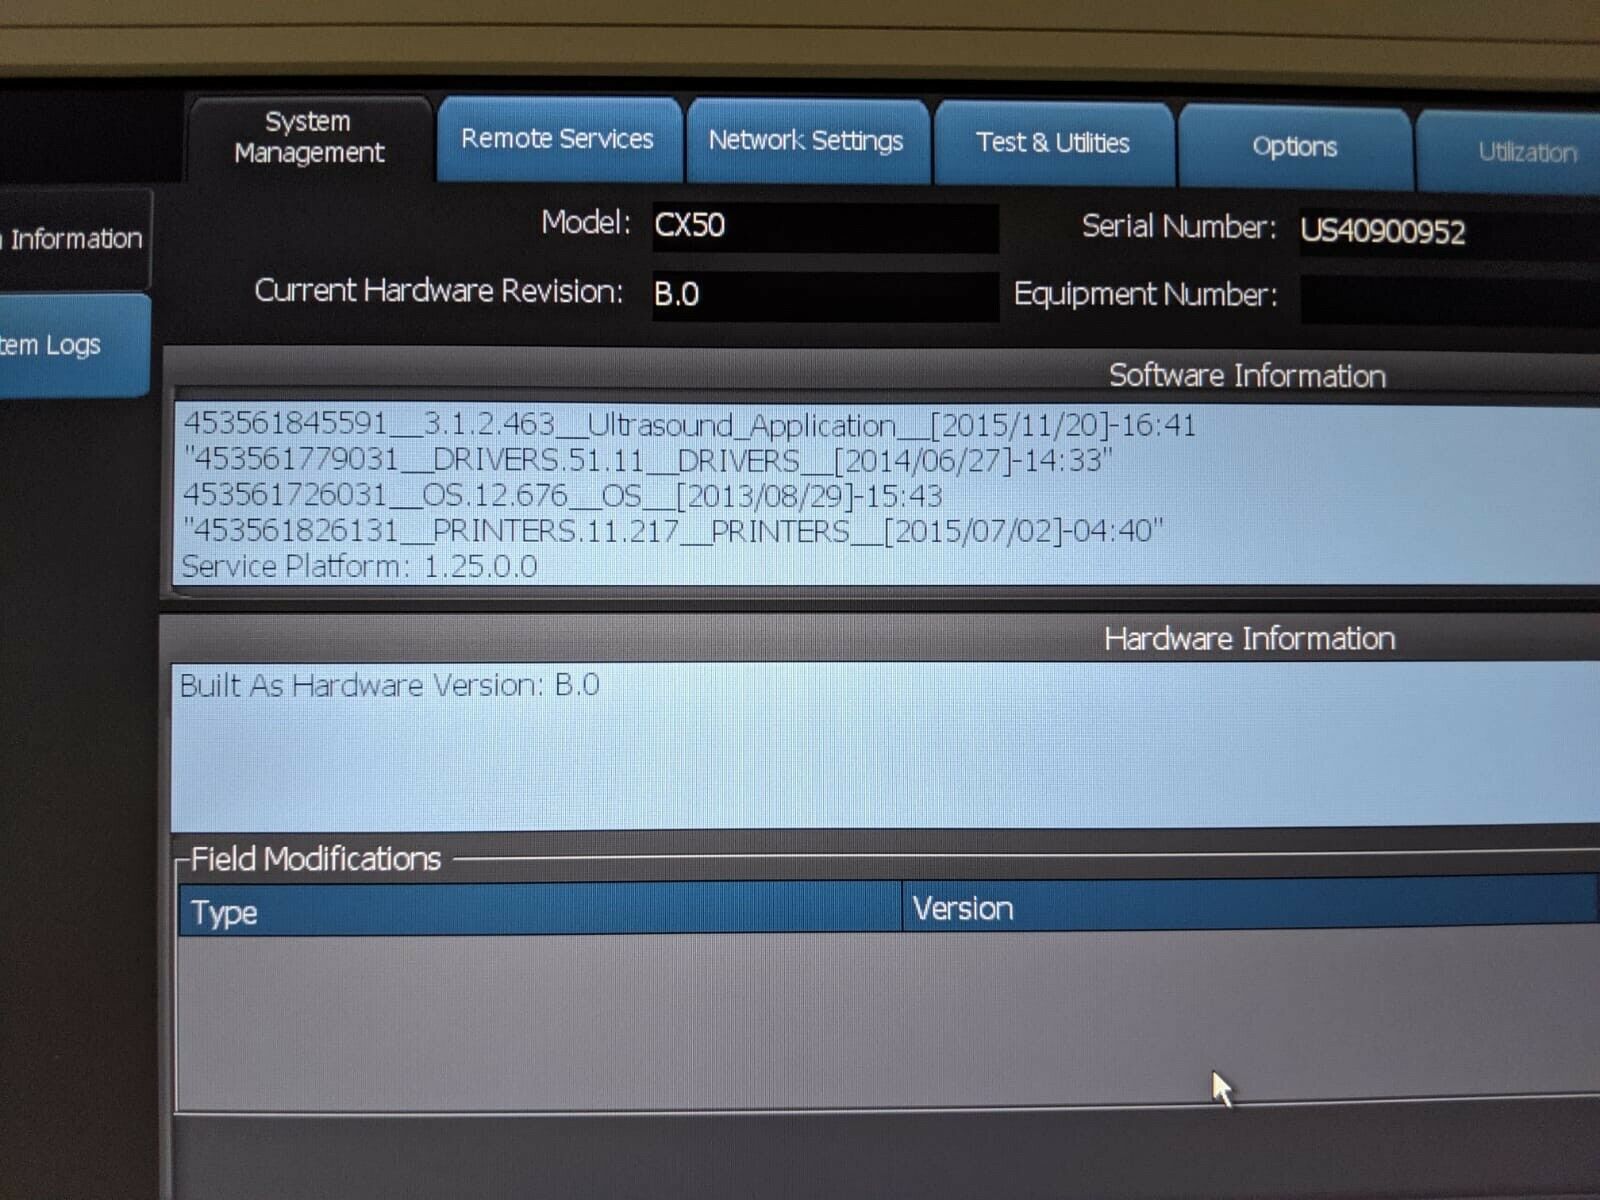

The Philips CX50 2013 Rev 4 Portable Ultrasound System with three probes is a high-performance imaging solution designed for flexibility across a range of clinical applications. This compact, portable ultrasound machine delivers premium imaging quality, making it ideal for point-of-care, cardiology, vascular, and emergency medicine. Equipped with Philips’ advanced imaging technologies like PureWave crystal technology, the CX50 provides exceptional resolution and detail, even in difficult-to-image patients.

The three included probes offer versatility, allowing clinicians to perform various exams, from cardiac and vascular to abdominal and superficial imaging. Its portability and lightweight design make it easy to transport between departments or use in field settings, without compromising on diagnostic accuracy. The CX50’s intuitive interface and customizable presets streamline workflows, making it user-friendly for fast-paced environments. This system is an excellent choice for healthcare providers needing a portable ultrasound solution that offers advanced imaging capabilities and multi-specialty support.